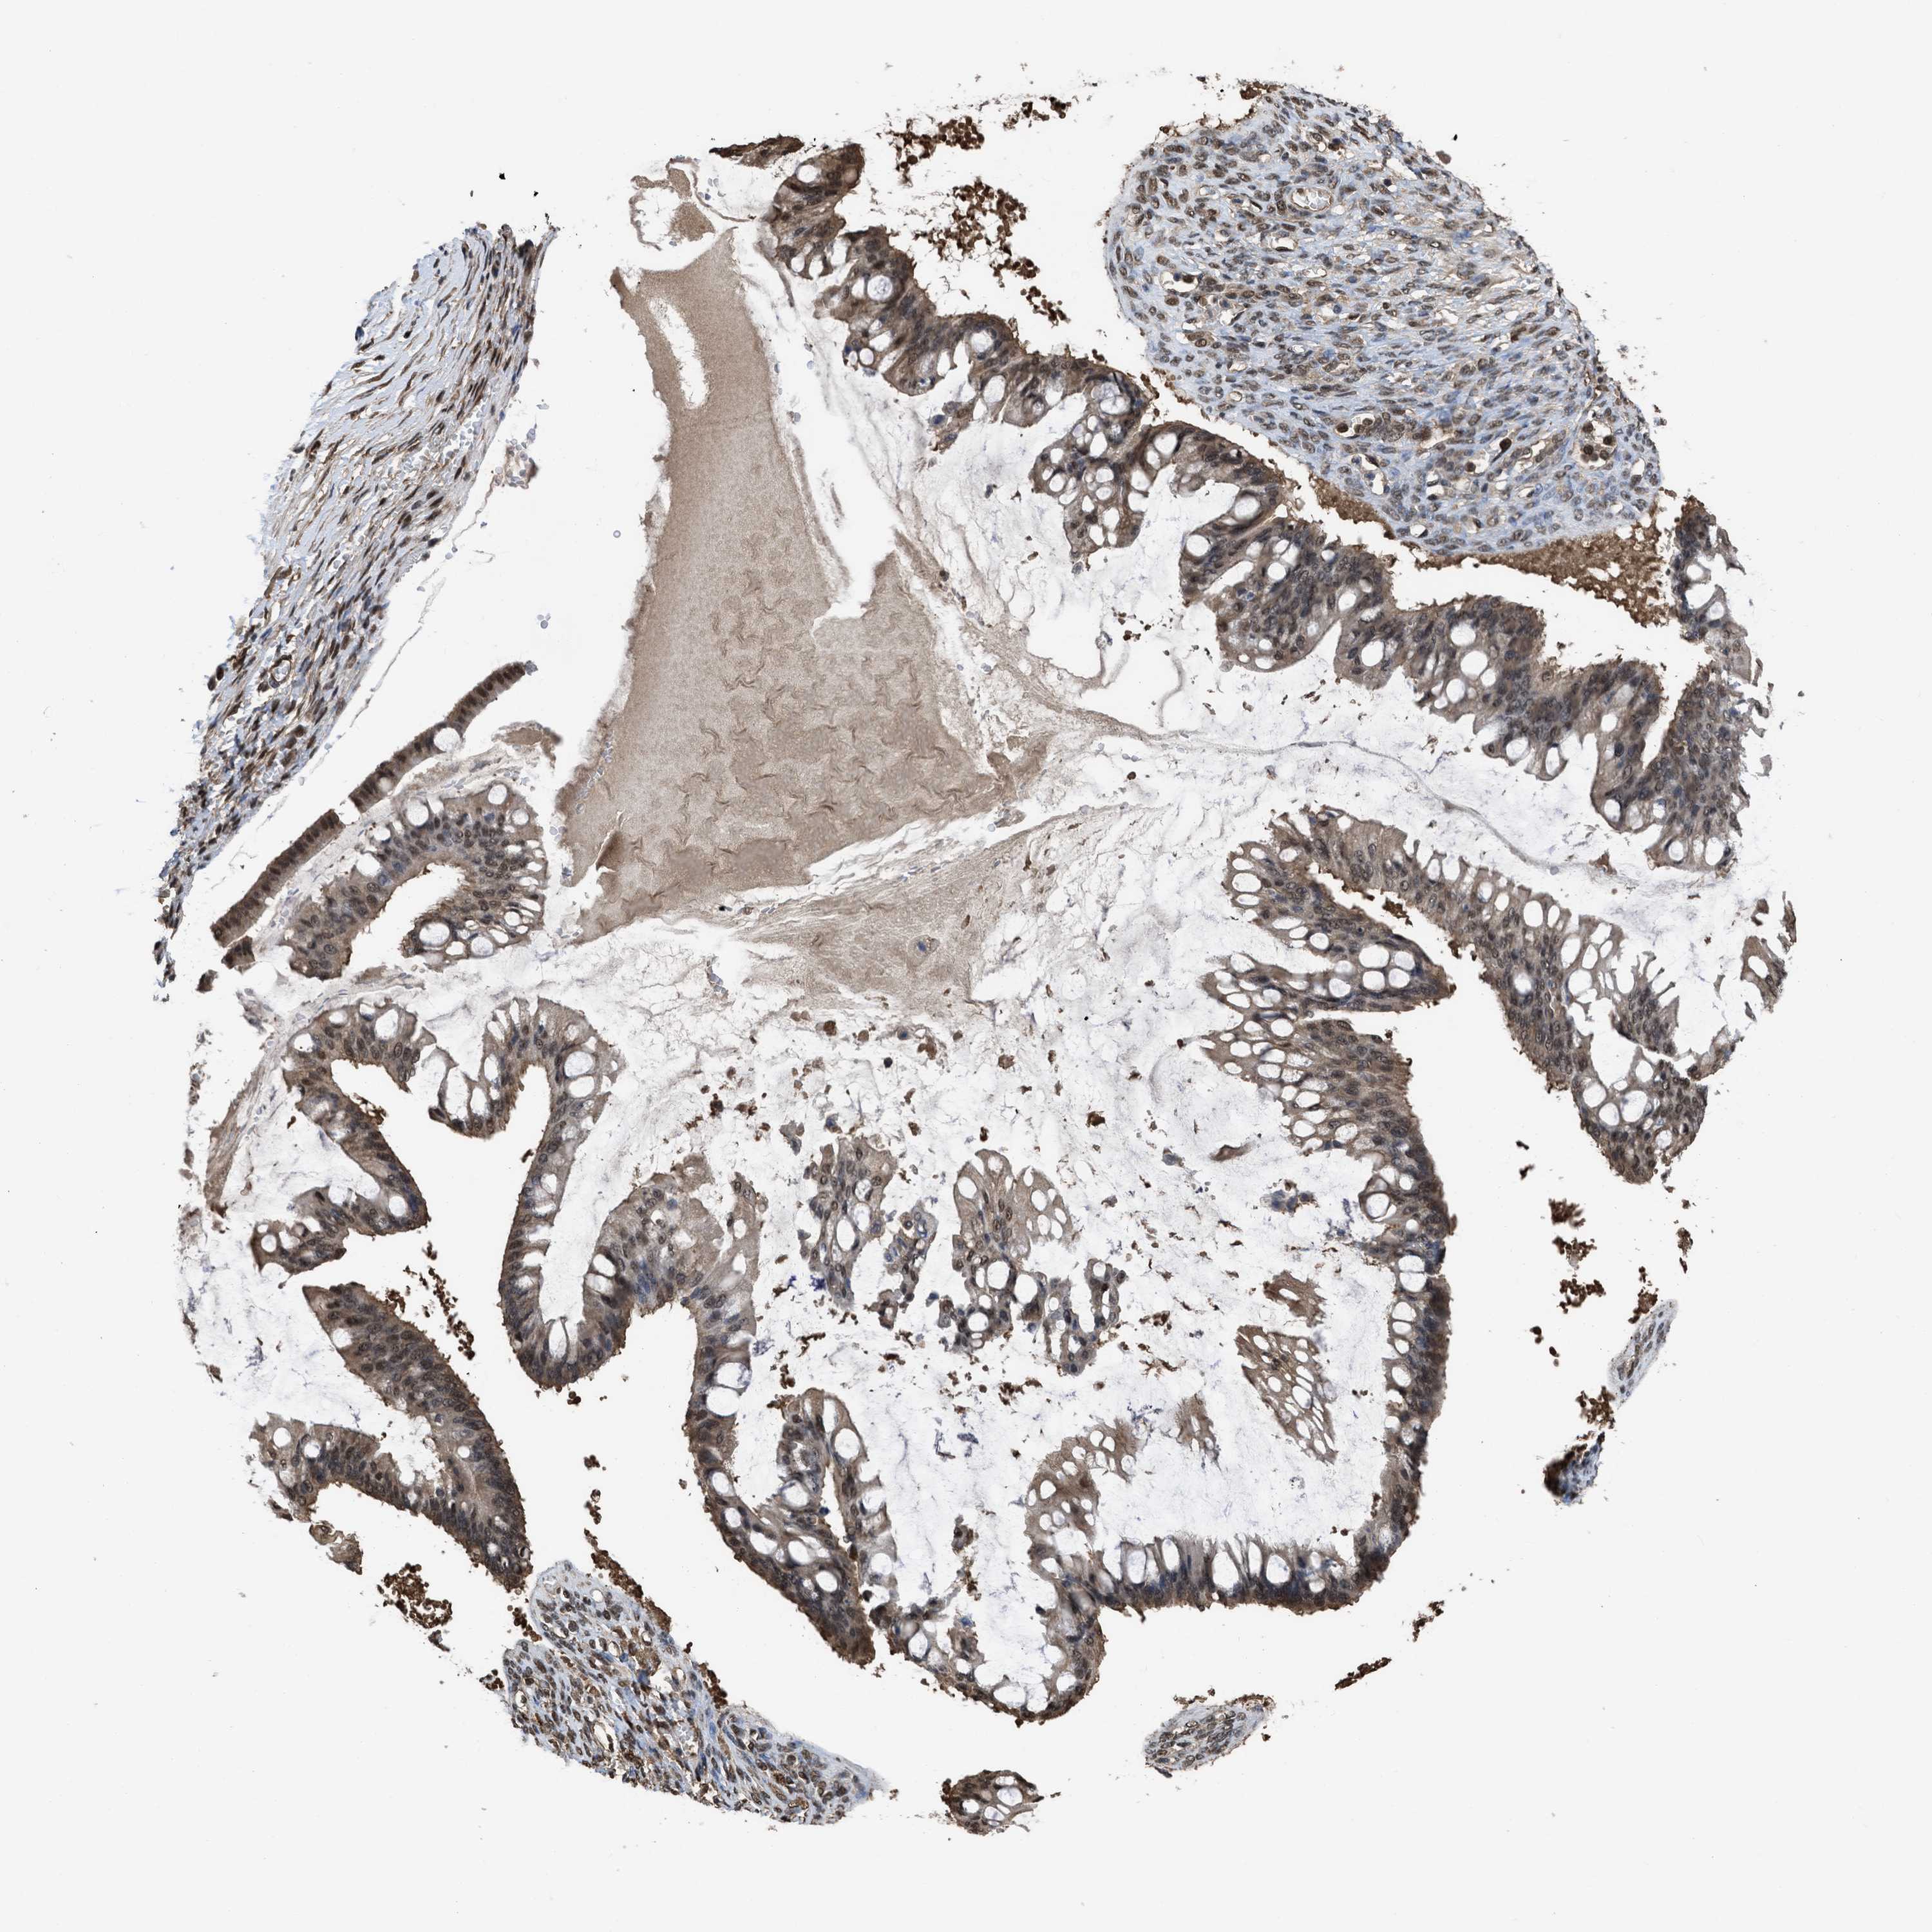

OVARIAN CANCER - Protein expressioni

A mouse-over function shows sample information and annotation data. Click on an image to view it in a full screen mode. Samples can be filtered based on level of antibody staining by selecting one or several of the following categories: high, medium, low and not detected. The assay and annotation is described here.

Note that samples used for immunohistochemistry by the Human Protein Atlas do not correspond to samples in the TCGA dataset.

Antibody stainingi

Antibody staining in the annotated cell types in the current human tissue is reported as not detected, low, medium, or high, based on conventional immunohistochemistry profiling in selected tissues. This score is based on the combination of the staining intensity and fraction of stained cells.

Each image is clickable and will lead to virtual microscopy that enables deeper exploration of all samples and also displays staining intensity scores, fraction scores and subcellular localization as well as patient and tissue information for each sample.

Antibody HPA026918

Antibody CAB013274

Antibody CAB018389

Cystadenocarcinoma, serous, NOS

Carcinoma, endometroid

Cystadenocarcinoma, mucinous, NOS

Carcinoma, NOS